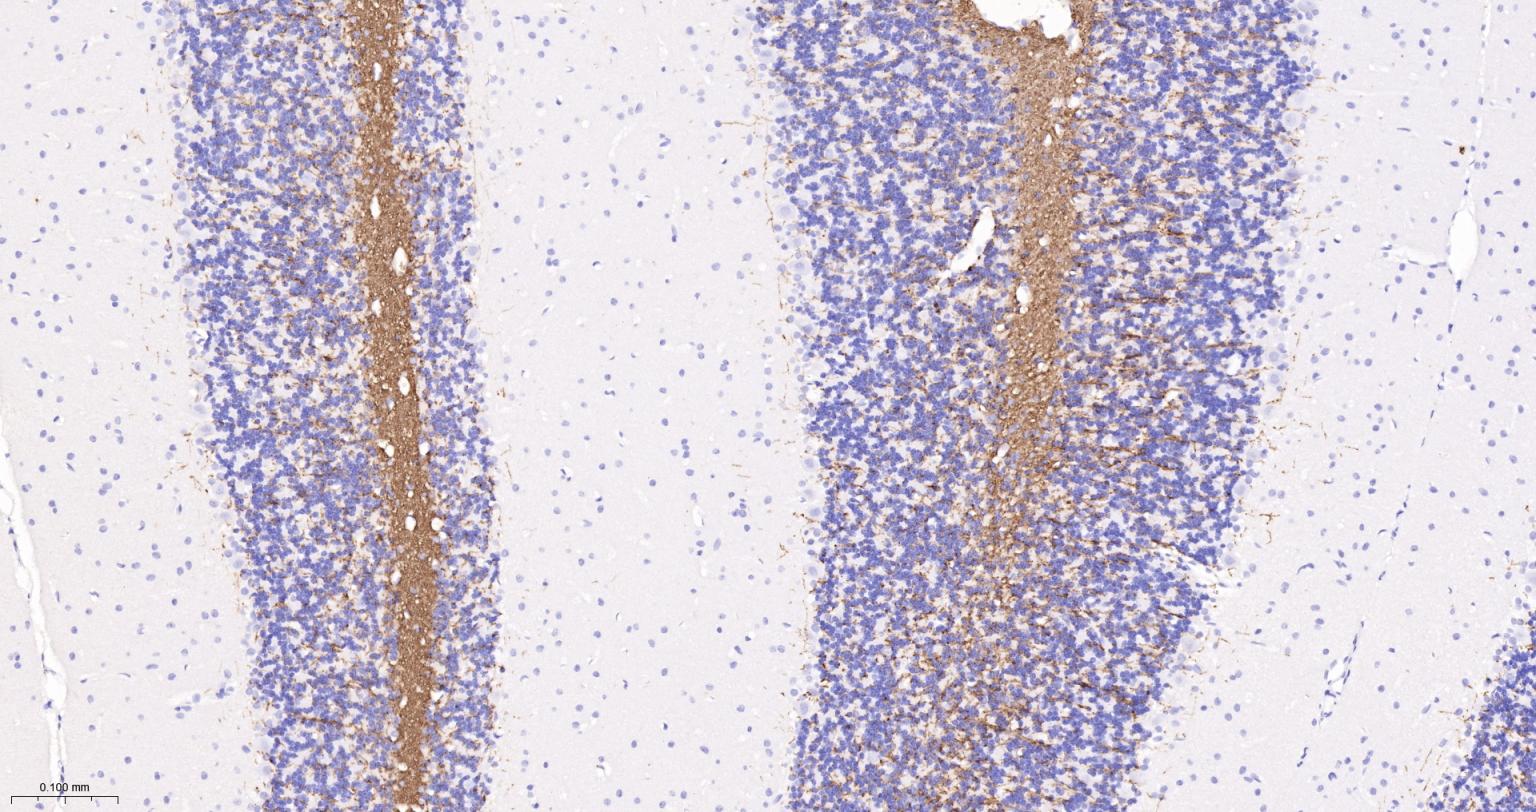

8. 显色

用吸水纸吸去玻片上多余的液体,在每张切片上滴加约50 μL新配制的DAB工作液(试剂7:试剂8:PBS=1:1:18),作用3-5 min。显微镜下观察结果,达到合适的显色强度后,用蒸馏水冲洗切片以终止反应,用蒸馏水冲洗5 min,重复3次。

| IHC-P | Human, Mouse, Rat | 1:200-1000 | |